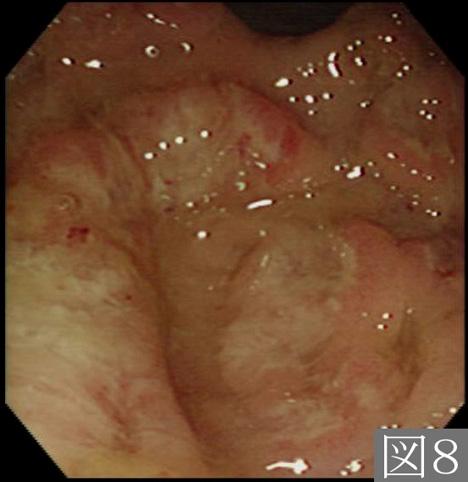

A case of amebiasis which showed the typical morphologic findings corresponding to the amebic colitis.

Enfermedad Inflamatoria - Ulcerativa/Disentería Amebiana

colon/lesión que abarca dos o más regiones del colon

Endoscopia